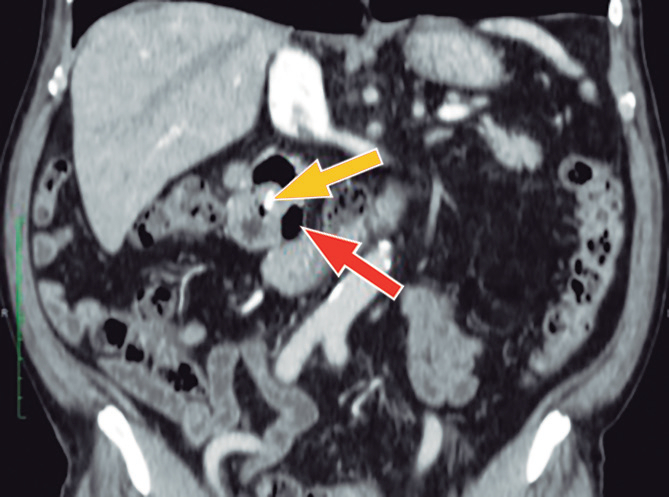

Con los hallazgos mencionados, se realizó el diagnóstico de colangitis grado II (sobre la base de los criterios diagnósticos y de severidad de las guías de Tokyo),6 y se inició tratamiento antibiótico. Posterior a las primeras 24 horas del diagnóstico, el paciente fue sometido a CPRE, en la que se identificaron tres divertículos duodenales periampulares. Debido a que la canulación fue difícil, tuvo que realizarse, durante el procedimiento, la técnica de rendez-vous (guiada por ecografía y fluoroscopía), utilizando el acceso transparietohepático para lograr el ingreso a la vía biliar. En la colangiografía, el conducto biliar se encontraba dilatado (10 mm) y no se evidenciaron imágenes por defecto de relleno. Se realizó una esfinterotomía mínima y se colocó una prótesis biliar plástica de 10 Fr x 7 cm para poder asegurar un adecuado drenaje de la vía biliar. El paciente evolucionó favorablemente. Al momento del alta no presentaba dolor abdominal, había normalizado los valores de leucocitos y PCR, y los valores de colestasis se encontraban en descenso. En los controles posteriores, el paciente presentó dolor abdominal esporádico en el CSD, pero el examen físico y los análisis de sangre no mostraron mayores alteraciones. El paciente contaba, además, con una tomografía abdominal con contraste, que no aportó información adicional a la evidenciada en la CPRM (Figuras 2 y 3).